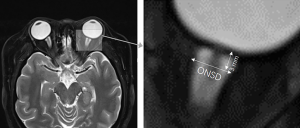

The optic nerve fiber belongs to a part of the central nervous system. It passes through the posterior scleral foramen, where the inner 1/3 of the sclera and the choroid from the lamina cribrosa (LC), and the outer 2/3 of the sclera evolves into the dura. The optic nerve is a part of the alba extending outward from the brain fiber and representing retinal ganglion cells (2,3). The posterior segment of the optic nerve is covered with 3 layers of meninges. The outer layer is the dura mater, the middle layer is the arachnoid mater, and the inner layer is the pia mater. There are 2 spaces between the 3 layers of the tunica vaginalis; the subdural space and the subarachnoid space (Figure 1). The front end of the 2 spaces ends at the back of the eyeball, forming a blind duct, and communicates directly with the brain space backward, full of CSF. The increase in ICP can be transmitted to the optic nerve sheath (ONS) space around the optic nerve through the CSF of the subarachnoid space so that the pressure of the latter also increases, resulting in the phenomenon of tortuosity and diameter increase (4). ONS dilation has been indicated to be an early indicator of ICP increase, so measuring the ONS diameter (ONSD) can detect whether there is an ICP increase and can be used to monitor changes in this increase (5).

MRI is another non-invasive method of ICP measurement that has received significant attention. MRI of the ONSD is similar to that of ultrasound, and the image is relatively clearer. MRI can also exclude ICP elevation caused by other potential reasons when performing optic nerve examination (51). Usually, the neuroimaging manifestations of intracranial hypertension include empty sella, tight subarachnoid spaces, retrobulbar flattening, ONS dilation, cerebellar tonsil herniation, meningocele, transverse venous sinus stenosis, and vertical tortuosity of the optic nerve (52-56). T2-weighted MRI was used to analyze the orbital structure and ONS. Most of the optic nerve reports about ICP came from thin sections of the orbit or volumetric fat-saturated T2-weighted images. The diameter of the axial and coronal positions of the 3-mm retrobulbar were averaged (57,58) (Figure 3). Compared with B-ultrasound, MRI has higher spatial resolution and can distinguish the optic nerve from tunica vaginalis, so the calculation of ONSD is more representative. A study of idiopathic intracranial hypertension (IIH), 5 patients with headache, blurred vision, and bilateral optic disc edema was examined by MRI. The results showed that the diffusion of the optic nerve head in both eyes was limited. After a lumbar puncture, it was confirmed that the CSF opening pressure was >25 cmH2O (59). The reason for this could be the compression of the central retinal artery and vein when ICP increased and may be a manifestation of increased ICP. Alperin et al. used another method to measure ICP, elastic index, which uses MRI to calculate the ratio of pressure to volume change. The principle of this method is that the derivative of volume to pressure decreases with the increase of ICP, and the ratio of the derivative is used to predict ICP (60). MRI-ICP software based on this principle makes calculations easier, and Alperin et al. used this method to estimate craniospinal compliance and improve supine and standing pressures (61). The pressure volume index measured by MRI was proposed to obtain the skull and spinal cord’s compliance index. It was found that the contribution of the spinal canal in IIH was significantly less than that in the normal control group (60% vs. 78%) (62). Moreover, as opposed to other imaging methods, MRI-ICP can also estimate the decrease of ICP. At present, in glaucoma-related studies, MRI-ICP is considered to be the most suitable choice to estimate low or normal ICP (63). However, MRI also has its limitations. It is impractical to transfer a potentially unstable critical patient for a long period, and frequent radiography will result in high costs (64).